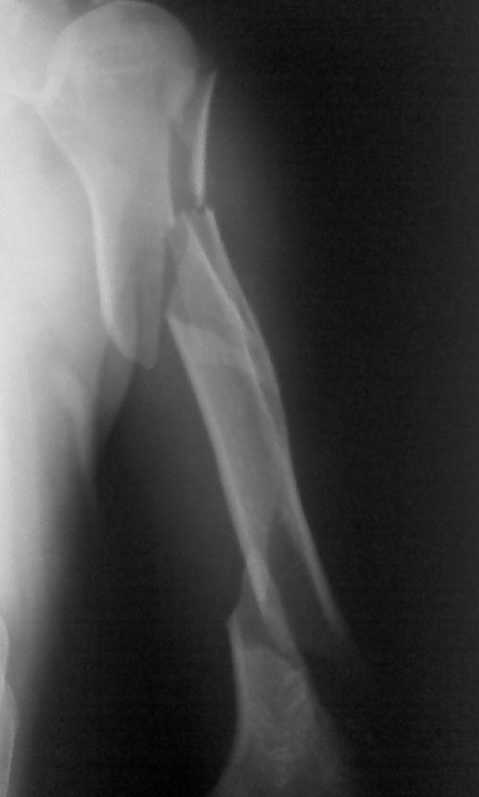

Мужчина 54 лет поступил в отделение в послепразднечные дни с вот

таким сложным и редким переломом плечевой кости (см. рентгенограммы).

Перелом получен во время эпиприпадка. Мы понимаем, что методом выбора

в данном случае является БИОС, однако в нашем лечебном учереждении

это исключено по разным причинам: во-первых, нет ЭОПА, а во-вторых,

администрация категорически против покупки фиксаторов больными

(вплоть до увольнения)- в таких условиях приходится "работать". В

нашем распоряжении есть обычные пластины, штифты Кюнчера, титановые

штифты (заготовки), аппараты Илизарова. Пока больше склоняемся к

выполнению остеосинтеза двумя пластинами: первая передне-наружным

доступом сверху, а вторая задним доступом снизу... Как вы смотрите на

этот вариант остеосинтеза, какие есть альтернативы исходя из наших